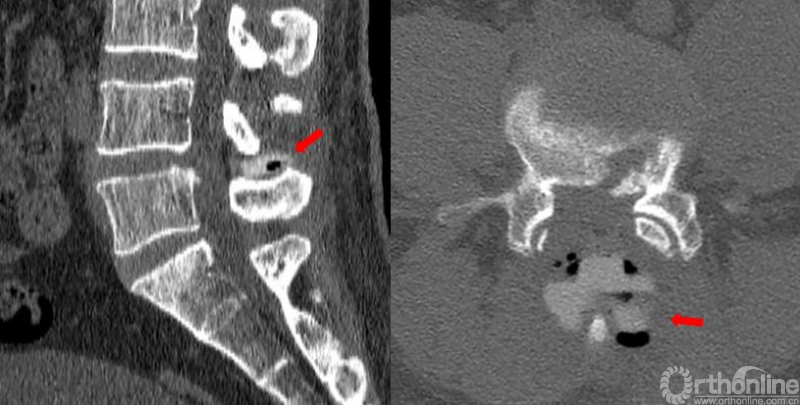

患者术后次日佩戴腰围下地行走后自觉右下肢疼痛症状明显缓解(术后右下肢VAS评分1分),结合我院围手术期ERAS(术后快速康复)的各项管理措施,患者取得了满意的临床疗效。术后复查腰椎CT显示(图5)减压充分明确,IntraSPINE内植物位置稳定可靠,患者生活质量明显改善。

图5. 术后复查CT:减压充分明确,IntraSPINE位置稳定可靠